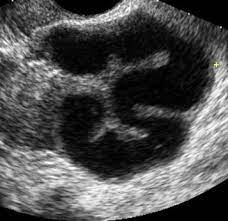

DiagnosticPentru a diagnostica sterilitățile de origine uterină se face apel la histerosalpingografie (radiografie a uterului și trompelor uterine), la histeroscopie (examen endoscopic al uterului pe căi naturale) și la celioscopie (examen direct al organelor genitale mulțumită unui tub dotat cu un sistem optic și introdus printr-o mica incizie în abdomen). Calitatea glerei este controlată prin testul lui Huhner (examenul unui prelevat de gleră recoltat la câteva ore după raportul sexual), eventual completat cu un test de penetrare încrucișată in vitro (comparație între două eșantioane de gleră, unul de la femeia în cauză și altul martor, puse ambele în contact cu sperma partenerului). Diagnosticul steriliăților de origine tubară se bazeză pe histerosalpingografie sau pe celioscopie. Sterilitatea de origine imunologică se diagnostichează în urma prelevării de gleră cervicală și a punerii în evidență a anticorpilor antispermatozoizi. În sfârșit, tulburările de ovulație pot fi relevate prin citirea curbei de temperatură care a fost luată în fiecare dimineață de către femeie. Această citire este completată cu dozarile sangvine ale hormonilor foliculostimulant (FSH) și luteinizant (LH), precum și a prolactinei între a 3-a și a 8-a zi a ciclului, si prin cea a progesteronului după ovulație.